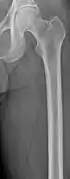

The diagnostic examination of a person with suspected multiple myeloma typically includes a skeletal survey. This is a series of X-rays of the skull, axial skeleton, and proximal long bones. Myeloma activity sometimes appears as "lytic lesions" (with local disappearance of normal bone due to resorption) or as "punched-out lesions" on the skull X-ray ("raindrop skull"). Lesions may also be sclerotic, which is seen as radiodense.[70] Overall, the radiodensity of myeloma is between −30 and 120 Hounsfield units (HU).[71] Magnetic resonance imaging is more sensitive than simple X-rays in the detection of lytic lesions, and may supersede a skeletal survey, especially when vertebral disease is suspected. Occasionally, a CT scan is performed to measure the size of soft-tissue plasmacytomas. Nuclear Medicine Bone scans are typically not of any additional value in the workup of people with myeloma (no new bone formation; lytic lesions not well visualized on nuclear bone scan).

- Femur with multiple myeloma lesions

- Same femur before myeloma lesions for comparison